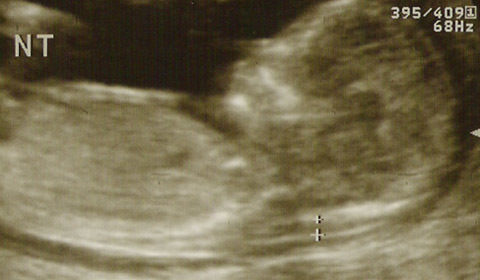

Hacia finales del primer trimestre de embarazo, alrededor de la semana 12, se indica a todas las embarazadas la realización del test de traslucencia nucal (TN), un análisis ecográfico en el que se medirá el pliegue nucal del feto.

Pero, ¿qué es pliegue nucal, cómo se mide y para qué? En la región de la nuca del bebé se acumula líquido de forma fisiológica y transitoria en esta etapa de la gestación. Esta acumulación puede verse por medio de una ecografía a partir de la novena semana de gestación y para obtener resultados fiables se mide entre la semana 10 y 14 cuando el feto tiene una longitud cráneo caudal, es decir de cabeza a culete, de entre 38mm y 84 mm.

Para medir el pliegue nucal el especialista busca que el bebé se coloque de costado de manera que pueda verse un corte longitudinal. Procede entonces a medir el espesor máximo de la translucencia subcutánea entre la piel y el tejido blando que recubre la columna cervical.

pliegue-nucal

El aumento de espesor de la traslucencia nucal, o sea cuando la medición supera el grosor de los 3mm, se asocia con un aumento del riesgo de anomalías cromosómicas. La acumulación excesiva de líquido puede ser explicado por una sobreexposición del colágeno del tipo VI codificado por un gen en el cromosoma 21. Es el marcador ecográfico precoz más sensible y específico de sospecha de Trismomía 21 o Síndrome de Down.

La ecografía de la semana 12, en la que se mide el pliegue nucal del feto, es una prueba de presunción o sospecha. El análisis ecográfico realizado por un medico especialista sirve para detectar indicadores de que el bebé pueda tener síndrome de Down. No se trata de una prueba diagnóstica, sino que determinadas imágenes detectables por ecografía suelen ser indicadoras de anomalías cromosómicas o del desarrollo. Así también se evalúa la presencia de hueso nasal y de un crecimiento del feto acorde a las semanas de embarazo.